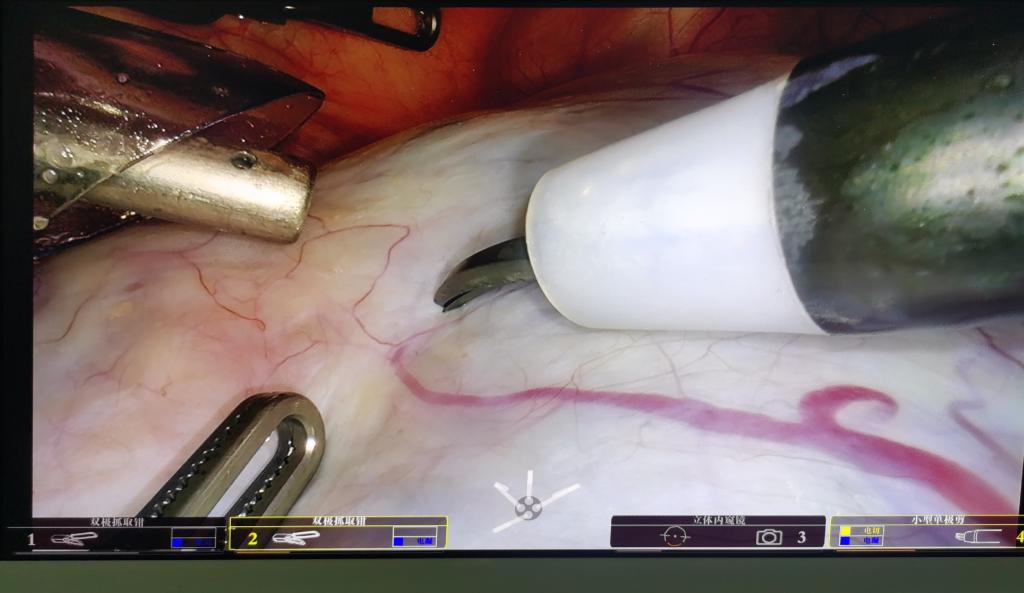

手术机器人术中视野

4月10日,二附院妇产科使用国内首台国产单孔机器人为一名34岁的患者施行巨大卵巢囊肿剥除及广泛肠粘连分离手术,手术过程顺利。该患者盆腔左侧卵巢囊肿近20CM,多房状,且合并盆腔器官囊肿、肠管之间广泛粘连。手术由妇产科主任薛翔教授主刀,既保留了双侧卵巢,也使广泛粘连的盆腔器官恢复了正常解剖,出血仅约20ml。手术既体现了单孔机器人手术精准分离的特点,又发挥了单孔机器人手术更易处理和取出标本的优势。